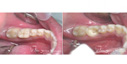

סתימות וציפויים - ד"ר ג'רי כהן